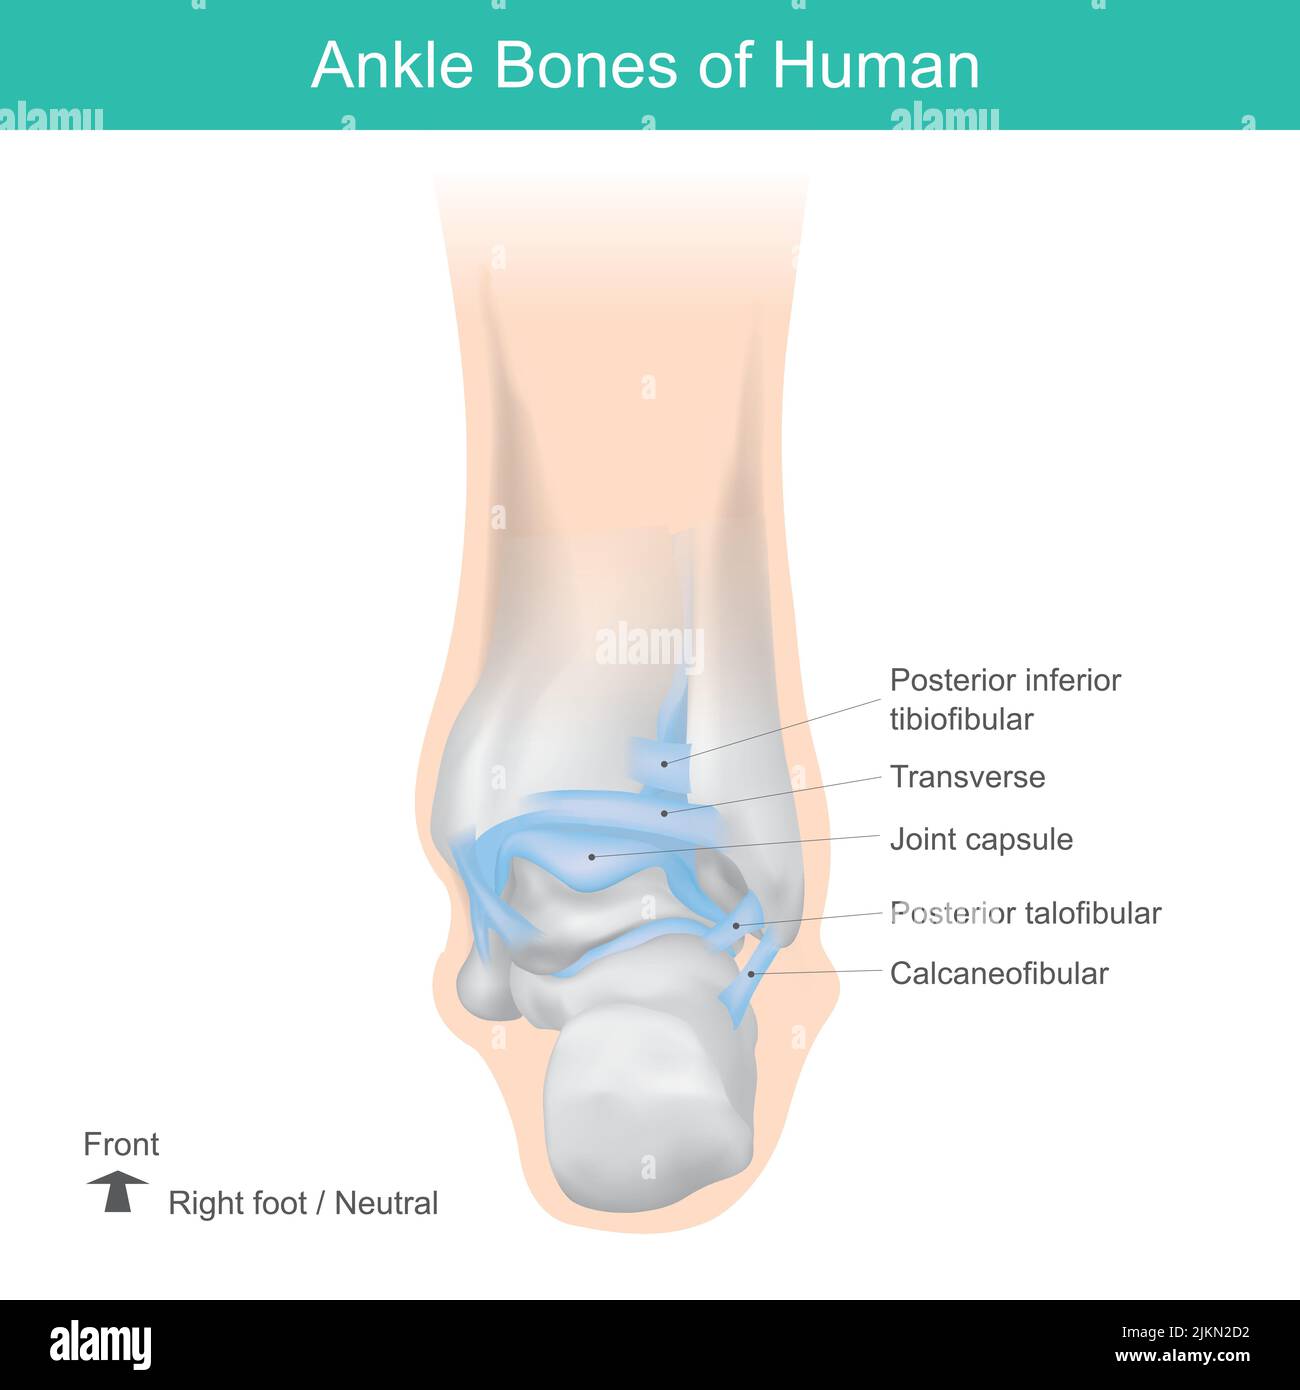

RF2JKN2D2–OS de la cheville humaine, position correcte os de la cheville humaine. Illustration Anatomy Health Care.

RFTCW7GT–L'articulation de la cheville, les tendons de la cheville anatomie pied eps vector illustration infographie 10